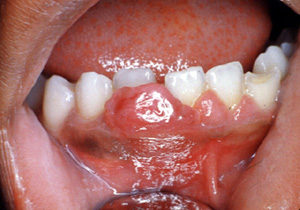

Este ejemplo es bastante vascular. Ha cambiado de sitio al incisivo central hacia lingual. Los granulomas de  celulas gigantes tienen un mayor potencial de crecimiento  que el granulomas periférico y puede cambiar de lugar  los dientes.

Aquí hay un ejemplo típico de un granuloma de celulas gigantes; sin embargo, sólo por la biopsia  escisional  es posible el diagnóstico.

Esta imagen ilustra bien cómo estas lesiones pueden crecer sin tratamiento. El hueso subyacente puede ser reabsorbido.